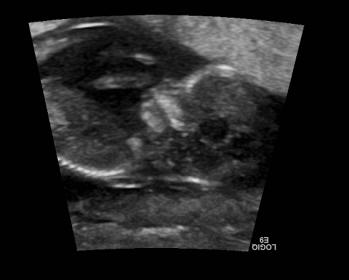

1st and 2nd pic is an internal ultrasound at 7 weeks